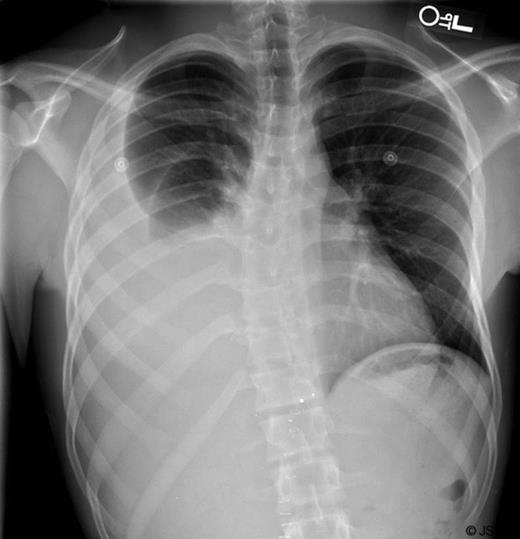

Six days later, the patient returned to the emergency department with complaints of right sided chest pain and worsening dyspnea. A plain chest film was performed (Figure 2) and demonstrated a large right pleural effusion. Computerized tomography of the abdomen also demonstrated several tiny retained metallic fragments embedded within the liver and retroperitoneum (Figure 3). A chest tube was inserted on the right side and immediately drained 2.2L of milky fluid (Figure 4).